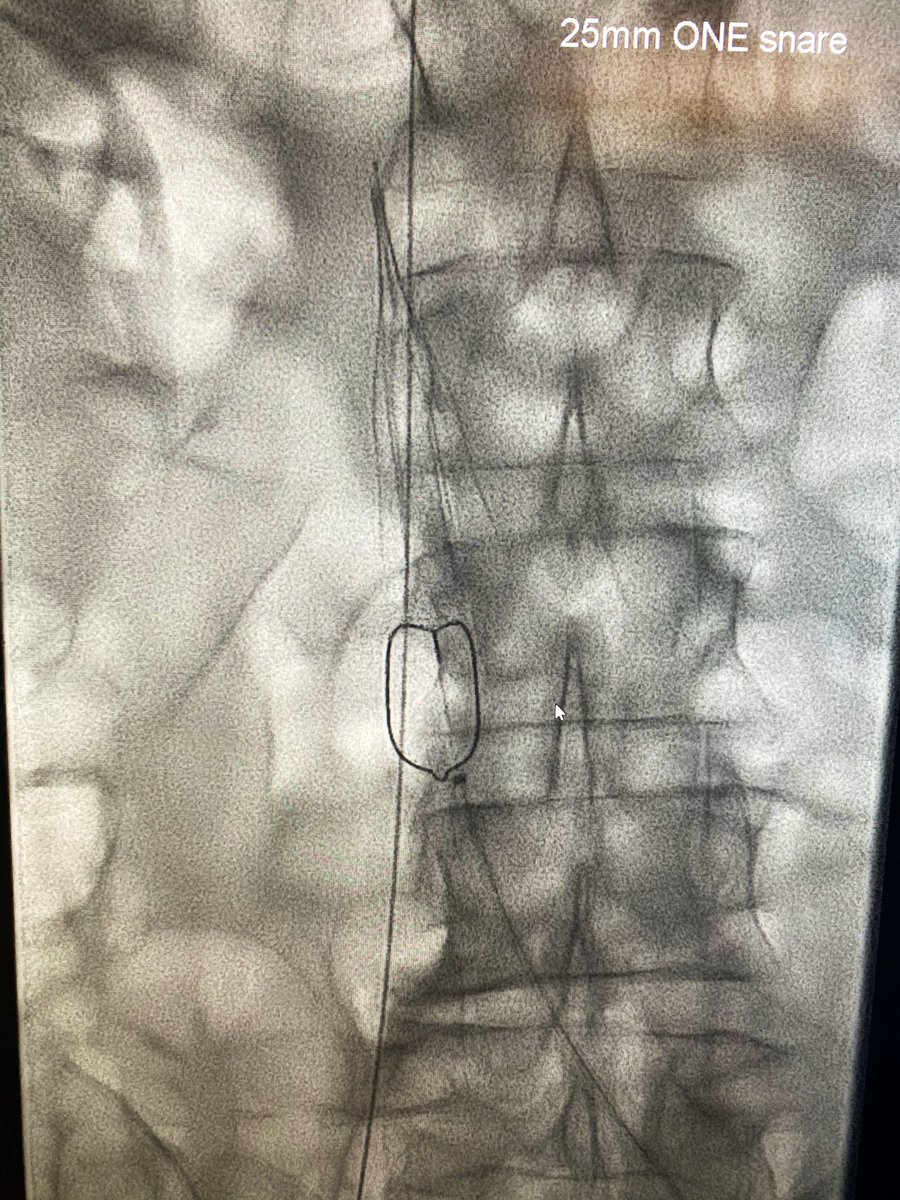

3 month old #IVCfilter with iliocaval occlusion, bilateral leg edema. Crossed both CIV occlusion from below, forceps #Filterout with 18Fr sheath then 18mm wallstent iliocaval reconstruction. #WeCanRecan